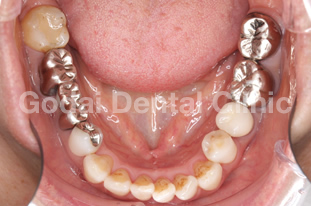

患者様は40代女性で、歯の痛みを理由に来院されました。育児を行いながら仕事をされている方で、毎日が忙しくなかなか歯科へ通う時間がなかったそうです。育児と仕事の空き時間を利用し、できるだけ通院が負担にならないよう、むし歯治療の計画を立てました。金属アレルギーがあることと、見た目もきれいにしたいという希望があったため、被せ物はオールセラミックスによる治療を選択し、小さいむし歯はコンポジットレジンによる詰め物で対応しました。限られた時間の中での通院でしたが、患者様と共に計画を立て治療を進めていくことで、最終的にとても満足していただくことができました。

術前上顎

術前下顎